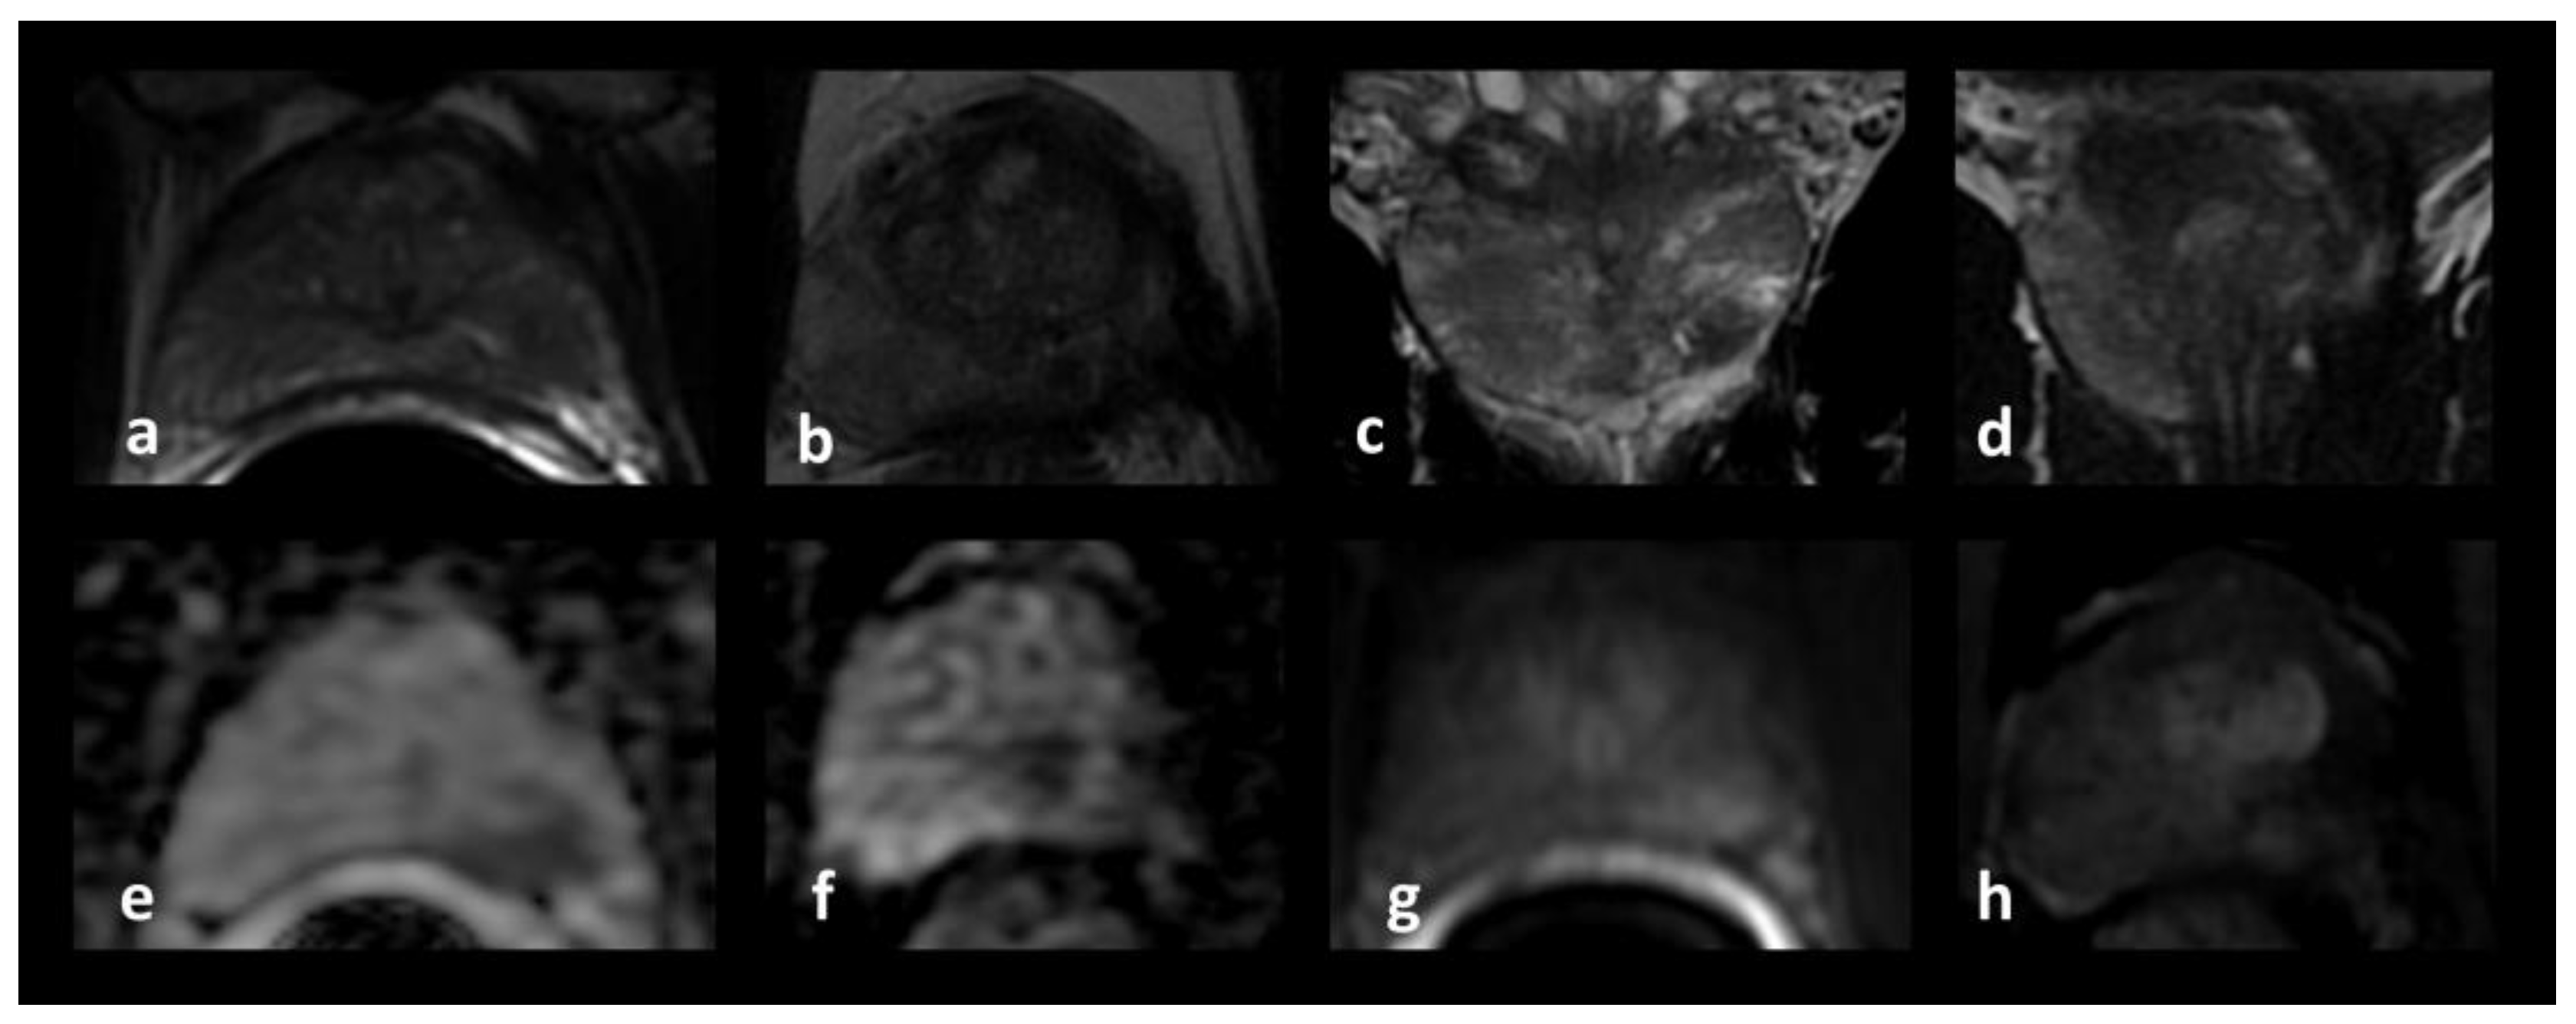

2.3.1. MRI–US Fusion Biopsies of the Index Lesion

2.3.2. Biopsies of the Area Surrounding the Index Lesion

2.3.3. Systematic Prostate Biopsy

2.3.4. Frozen Section

2.3.5. Procedure Planning

2.3.6. Cryoprobe and Thermocouple Placement